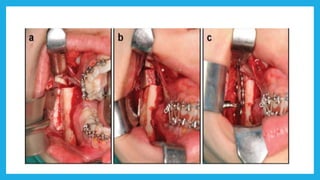

Ramus procedures  Bilateralsagittal split osteotomy(BSSO)

 Vertical subsigmoidosteotomy (VSS)